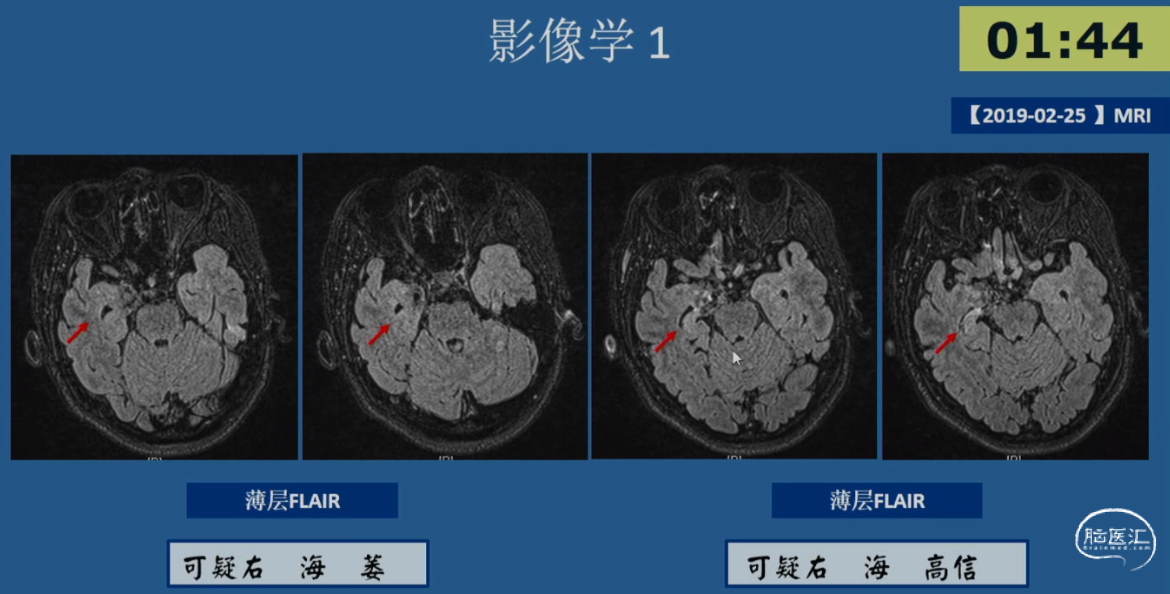

病例示例3 -简要病史

•患者,女性,20岁,右利手

•起病年龄:出生4月

•主要发作形式:伴有知觉受累的局灶性发作

-发作主要表现:发作前偶伴心悸、胸闷→后出现意识丧失伴眼神呆滞→数秒后出现身体向各方向不自主扭转,伴喉部发声(无四肢抽搐表现)→发作持续5-10min后意识恢复→发作后无头痛、头晕等不适

-【出生4月起】:初始发作频率1次/天,服用CBZ后发作可控;

-【12岁起】:发作频率再次↑为1次/天,加用药物后发作控制于5-10次/年;

-【19岁起】:多药联用控制不佳,发作频繁时可达3-4次/天,至少2-3次/月

•20岁时AEDs服用:CBZ 0.2g tid + LTG 100mg bid +CZP 0.5mg qn po

•既往史及家族史无殊,无热性惊厥史

•出生史:剖腹产,无早产、难产史,生长发育同同龄人;学历中专

•认知功能测评:MMSE 27分(延迟记忆-3),MoCA 27分(抽象-1,延迟回忆-2);WAIS-RC IQ 100分(语言IQ 92分;操作IQ 112分)

•情绪测评:HAMA 9分(轻度焦虑),HAMD 8分(轻度抑郁)

01.初步评估:

影像学表现:2018-03-05 MRI 常规MRI阴性